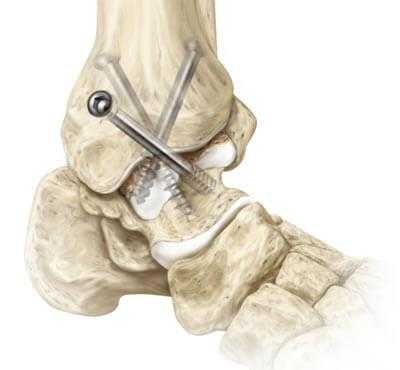

— Для обнажения медиальной лодыжки выполняется заднемедиальный разрез , который также лучше всего подходит для восстановления заднемедиального фрагмента голени.